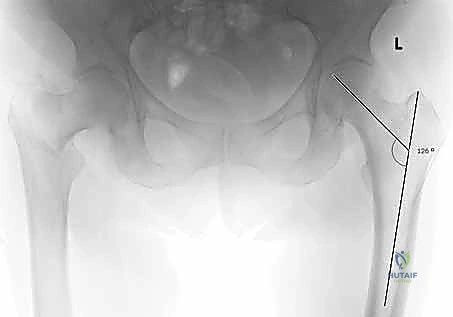

التصوير الطبي المتقدم

- الأشعة السينية (X-rays): هي المعيار الذهبي الأولي. يتم أخذ صور من الأمام للخلف (AP) وصور جانبية (Lateral) للحوض والورك المصاب. تكشف هذه الصور عن موقع الكسر، نوعه (بسيط أم مفتت)، ودرجة الإزاحة.

مجموعة من الصور الإضافية التي توضح مراحل دقيقة من العمل الجراحي المعقد الذي يجريه الأستاذ الدكتور محمد هطيف لضمان أعلى درجات الدقة الميكانيكية الحيوية: